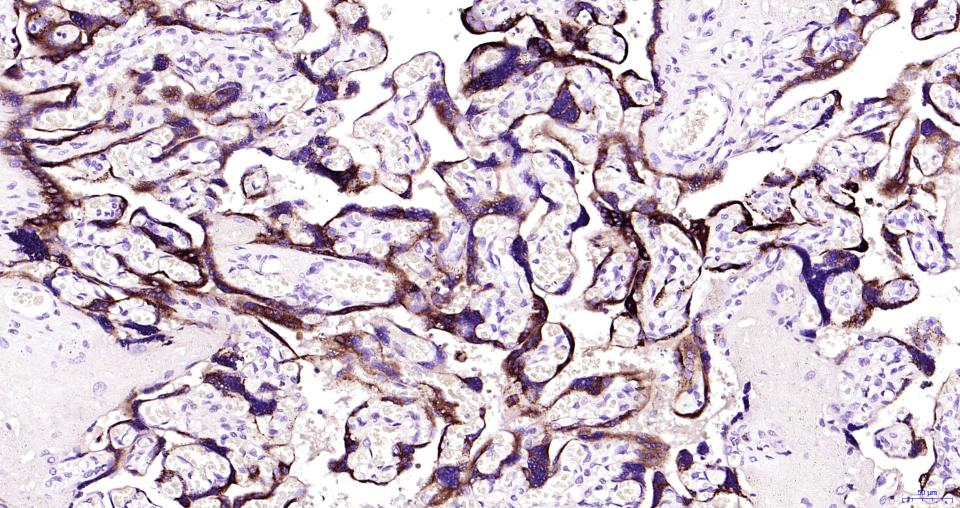

Paraformaldehyde-fixed, paraffin embedded Human placenta; Antigen retrieval by boiling in sodium citrate buffer (pH6.0) for 15 min; Antibody incubation with Human CG beta Monoclonal Antibody, Unconjugated(bsm-43172M) at 1:200 overnight at 4°C, followed by conjugation to the bs-40296G-HRP and DAB (C-0010) staining.